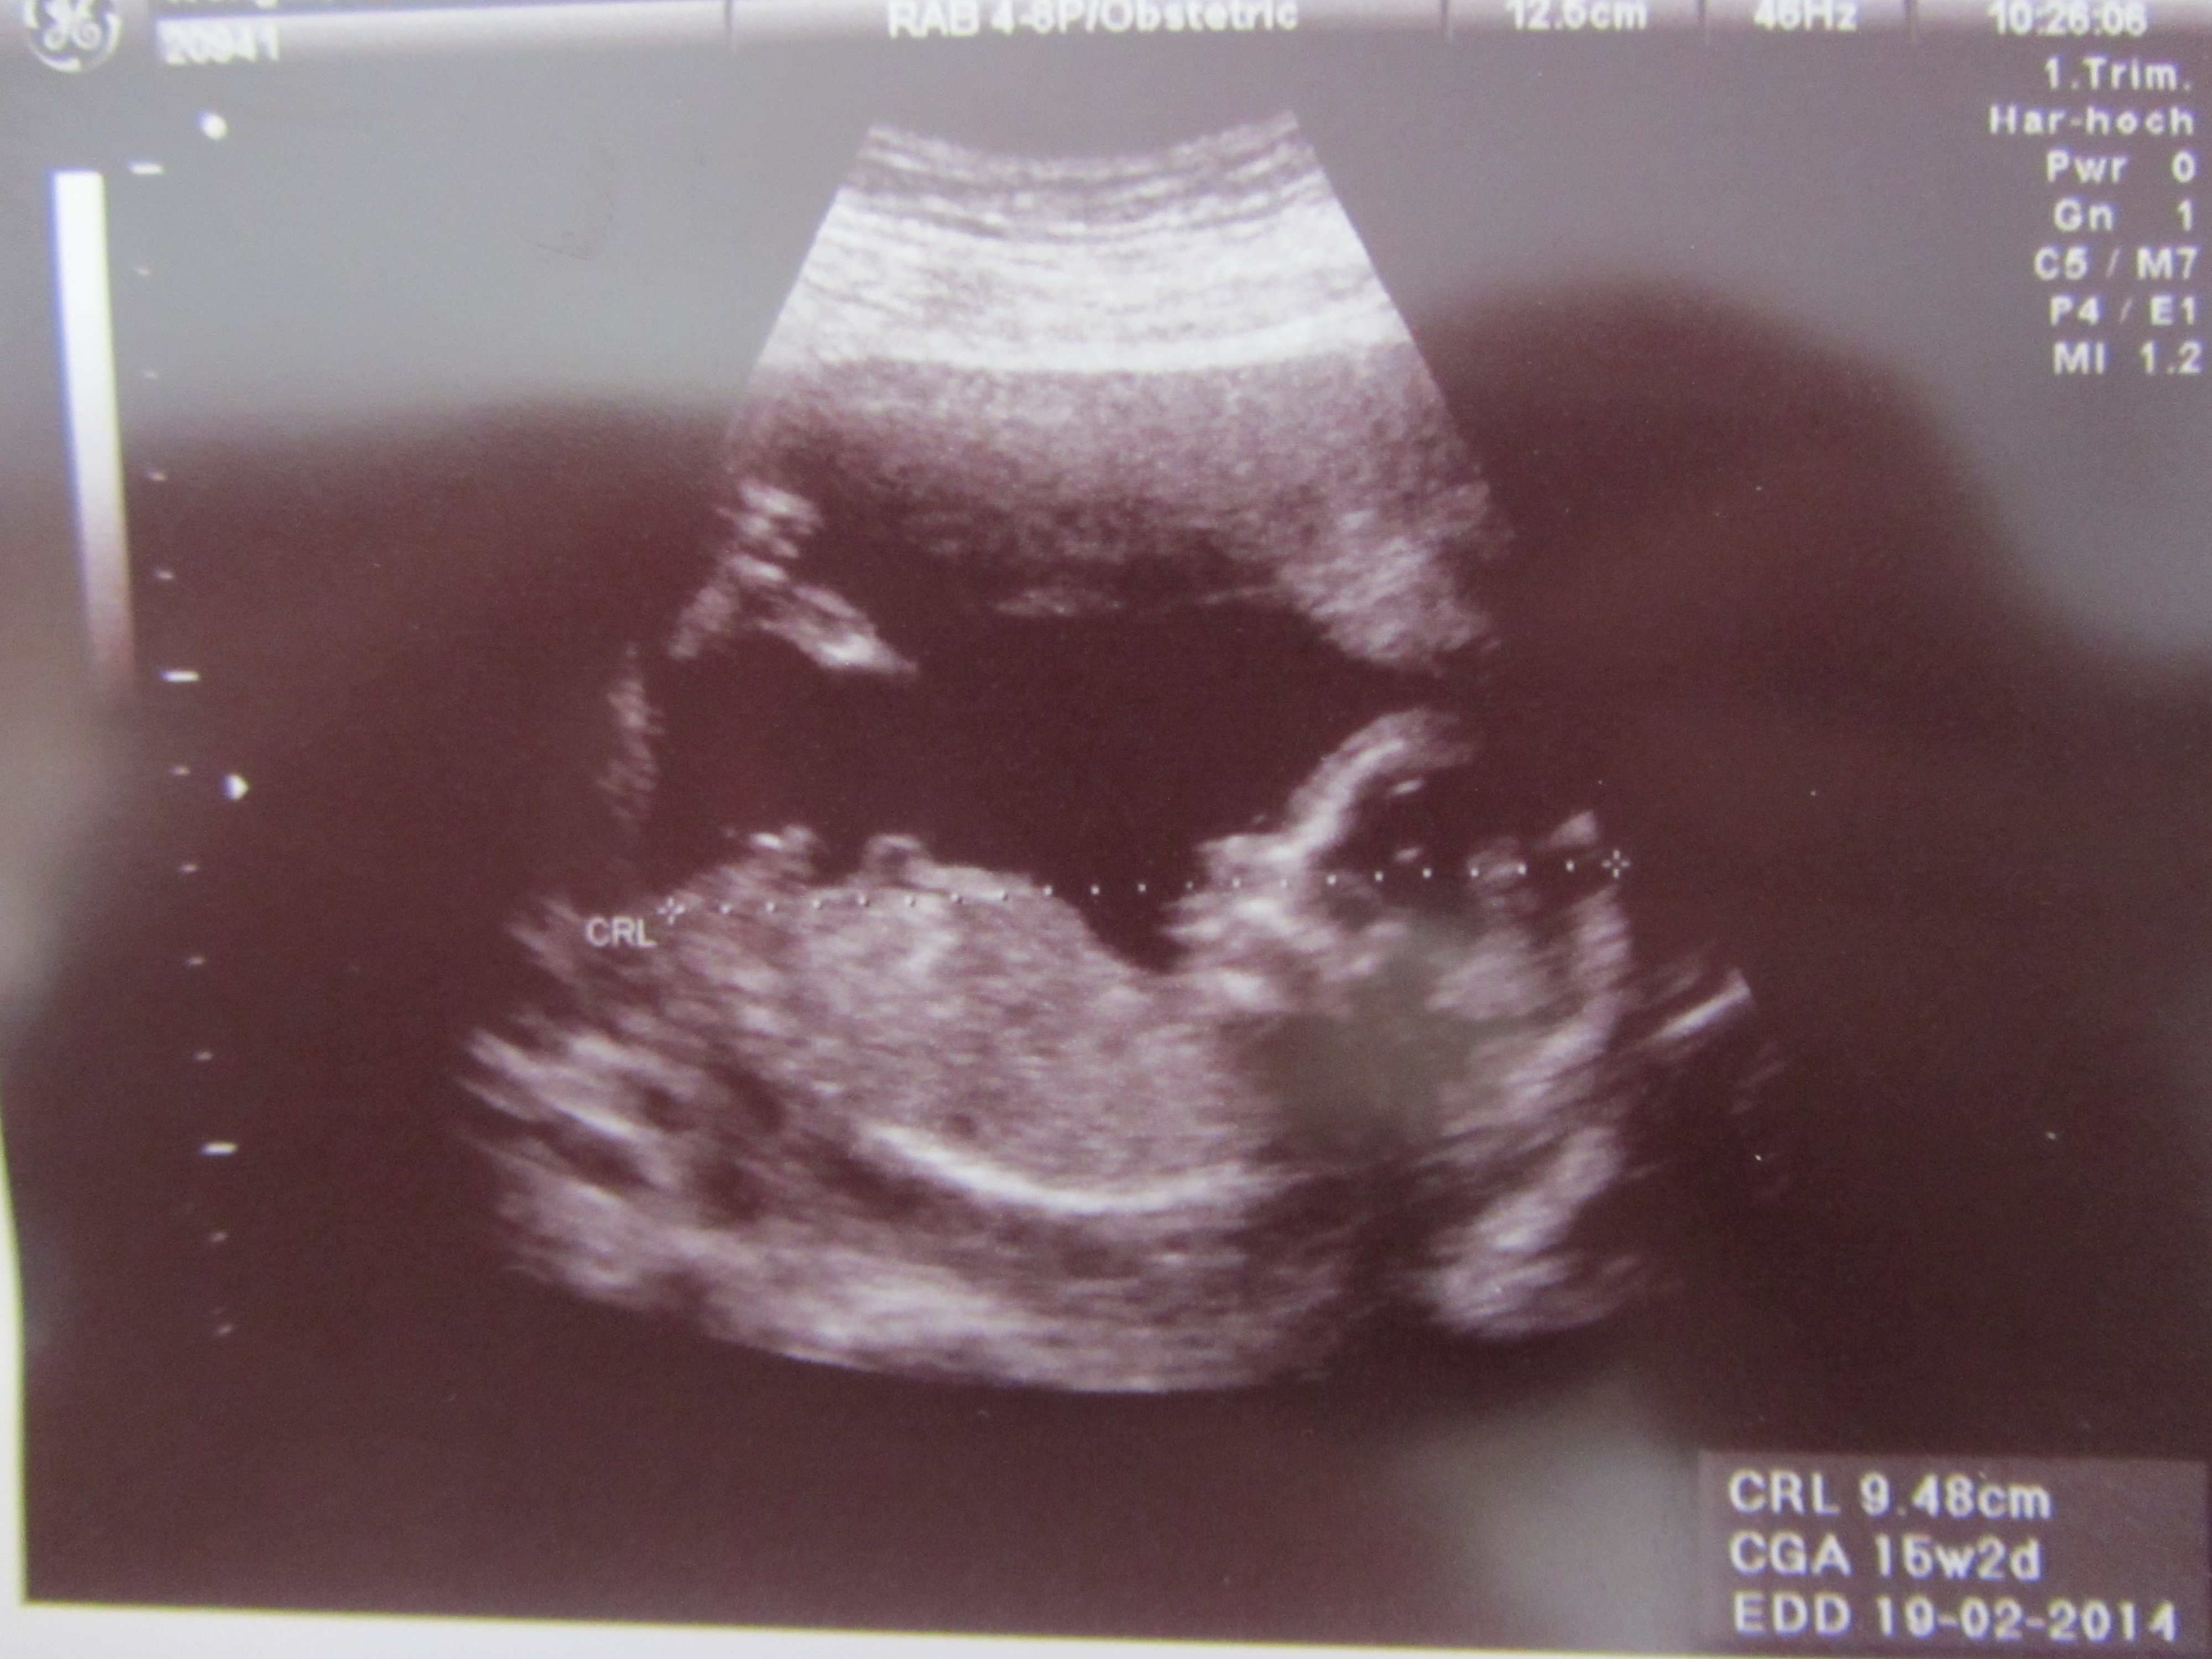

Here are my latest scans at 15 weeks 2 days. What do you all think? Girl or boy? My doctor said it SHOULD be a boy, but I wanted some other eyes to look at the pictures. Thanks!!

All boy. Congrats!

Definitely a boy nub. Congrats! x

Boy in both pics! Congrats!

Thanks, everyone. I think what confuses me are those two little lines at the end of his penis in the second picture "potty shot."